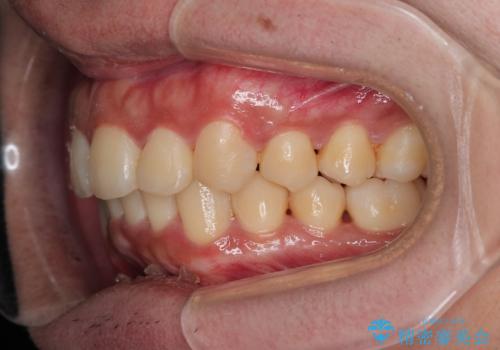

がたつきが気になる。インビザラインでスッキリ。

- インビザラインモデレート

- 奥歯の噛み合わせは特に問題ないため臼歯を特に大きく動かす事はなく。

歯と歯の間を削る(ディスキング)、拡大を行いマウスピースで矯正を行いました。

がたつきもなくなりスッキリした歯並びになりました。

がたつきが無くなると歯ブラシがしやすくなり汚れが溜まりにくい口腔環境ができます。